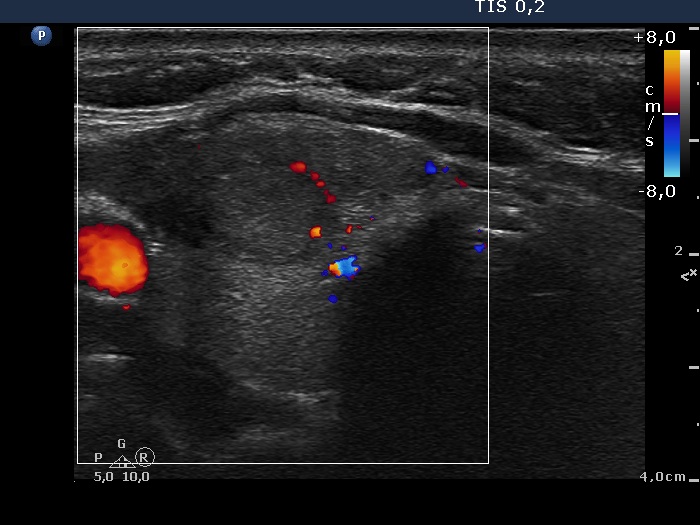

Ultrasound. The thyroid was echonormal. There was a moderately hypoechogenic mass located in the ventral surface of the right lobe. It was equivocal whether the lesion was within or outside the thyroid.

The ultrasound appearance of the lesion was unusual. We could not decide whether this lesion is within or outside the thyroid. Although more than 80% of such cases proves to be of thyroidal origin, additional tests are required to decide te issue.

The result of wash-out decided the question.